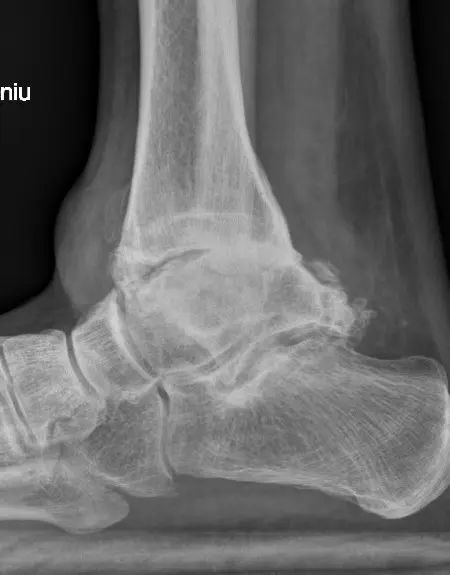

Obraz RTG stawu skokowego z zaawansowanymi zmianami zwyrodnieniowymi, w wyniku przebytego urazu – widok od przodu